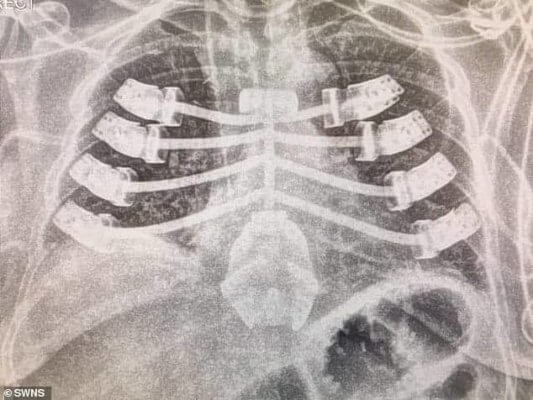

Bishay fertigte ein Sternum (Brustbein) additiv. Er ersetzte einen Teil ihres beschädigten Brustkorbs durch die 3D-gedruckte Titanprothese. Der Eingriff wurde im Juli 2019 von einem von Stephen Rooney geleiteten Herzteam am Queen Elizabeth Hospital durchgeführt. Edwards erholte sich schnell von der Operation, muss aber eine Zeit lang noch Medikamente nehmen.

Er beschrieb sein Implantat aus Titan als infektionsresistent, leicht, robust und funktionell. Ein ähnliches Verfahren hatte Bishay bereits 2017 im Heartlands Hospital in Birmingham durchgeführt. Dabei wurde ein Brustbein durch ein 3D-gedrucktes Implantat ersetzt. Das Metallimplantat war von Anatomics, einem australischen Hersteller von Medizinprodukten. Die CSIRO, die nationale Wissenschaftsagentur Australiens, war am 3D-Druck beteiligt.